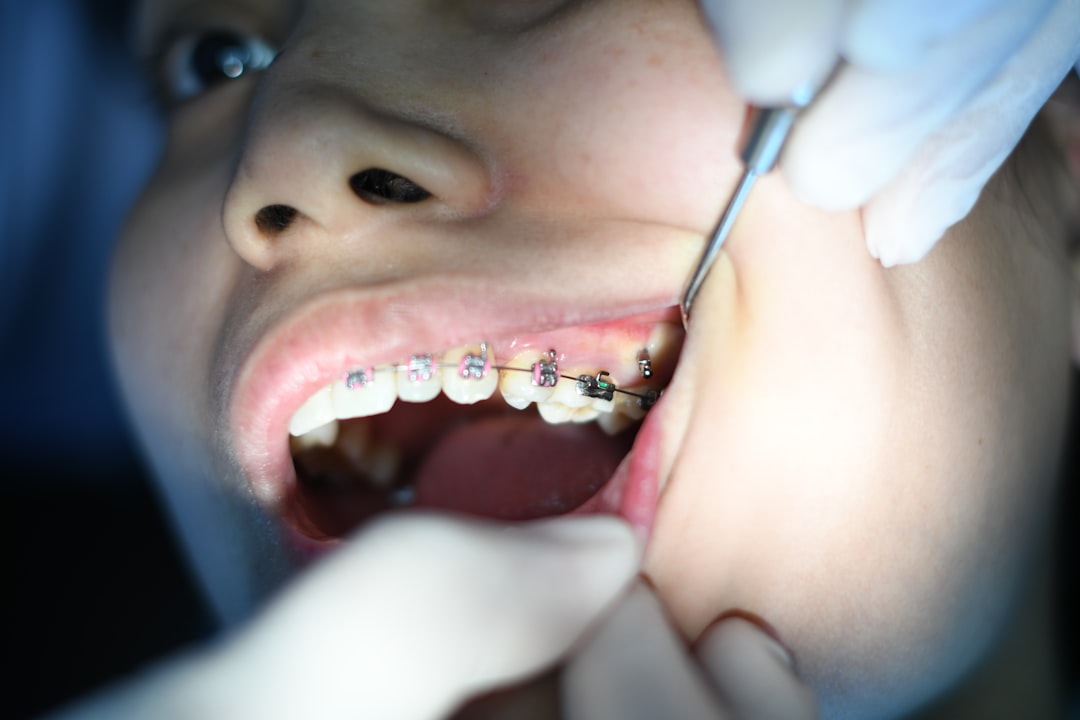

치아는 우리의 외모와 건강에 많은 영향을 미칩니다. 사람들이 자신을 표현할 때, 밝은 미소는 무언가 특별한 감정을 전달하죠. 그래서 치아 치료의 필요성을 간과할 수 없습니다. 하지만 치아 치료는 종종 비용이 많이 듭니다. 그런 점에서 라이나생명 치아치료는 특히 주목받고 있습니다. 보험상품으로 제공되는 다양한 보장 항목은 우리의 치아 건강을 지키는 데 도움을 줍니다. 그러니 이 기회를 통해 라이나생명 치아치료에 대해 알아보겠습니다.

라이나생명 치아치료는 여러 가지 보장 내용을 통해 우리의 걱정을 덜어줍니다. 첫 번째로, 일반적인 치료에 대한 보장이 있습니다. 여기에는 충치 치료, 신경치료 등 기본적인 치과 치료가 포함됩니다. 라이나생명 치아치료는 이러한 기본적인 치료를 보장하여 부담을 느끼지 않도록 합니다. 그리고 이 외에도 다양한 치료 방식이 포함되어 있는 점이 특징입니다.